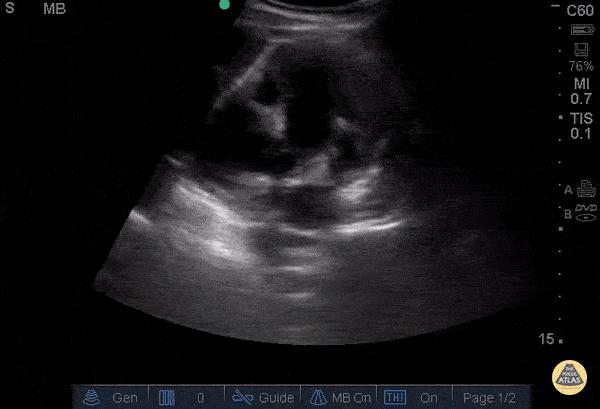

Renal/GU - Severe Hydronephrosis - Congenital

16 yo F who is known to have non-neurogenic neurogenic bladder, HTN. Presented to ED with severe bilateral flank pain for 2 weeks, worsening, dull in nature, associated with decreased urination, nausea, vomiting multiple times of food contents. Exam showed severe diffuse abdominal tenderness with bilateral CVA tenderness with light touch. POCUS showed bilateral severe hydronephrosis (L>R) without bladder enlargement. Labs showed elevated creatinine from 1 into 3. Patient then transferred to outside hospital for Pediatric Urology. Dr. Maan Al Dubayan - Kings County Emergency Medicine